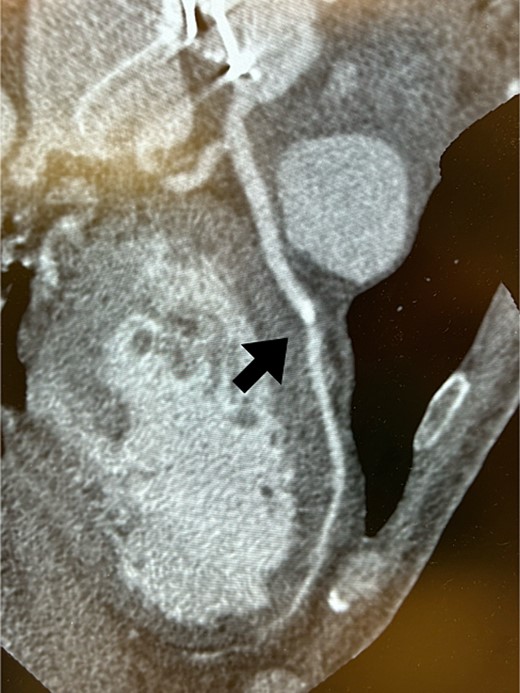

Postoperatively, an electrocardiogram revealed anterior ST-segment elevation, indicative of myocardial ischaemia. The patient then developed renal insufficiency. Given his haemodynamic stability, he was initially managed using coronary dilators and heparin. To improve renal function, coronary angiography was performed on the 10th postoperative day, which revealed a filling defect and 90% stenosis in the LAD artery (Fig. 1). Computed tomography (CT) revealed a high-density mass in the LAD artery with a mean CT value of 400 Hounsfield units (HUs) (Fig. 2). These findings indicated embolism, possibly due to a pledget from a previous surgery. A transcatheter approach was employed to remove the embolus, which was successfully extracted using a snare (Fig. 3a). Angiographic assessment revealed that the previously stenotic LAD demonstrated full perfusion, consistent with a thrombolysis in myocardial infarction (TIMI) flow grade of 3 (Fig. 3b). The patient recovered from catheterization without complications.

Coronary angiography detected 90% stenosis in the LAD artery; the arrow indicates the filling defect.